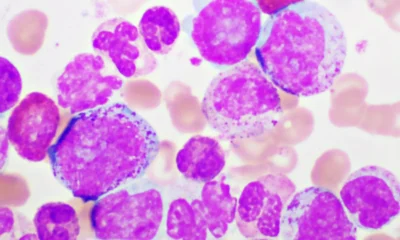

BioPharma Dive – AI / Data3 months agoMerck to buy Terns in $6.7B bet on a ‘differentiated’ leukemia drug

If consummated, the deal would hand Merck a treatment that could challenge Novartis’ fast-selling Scemblix. But the low purchase premium — which one analyst described as...